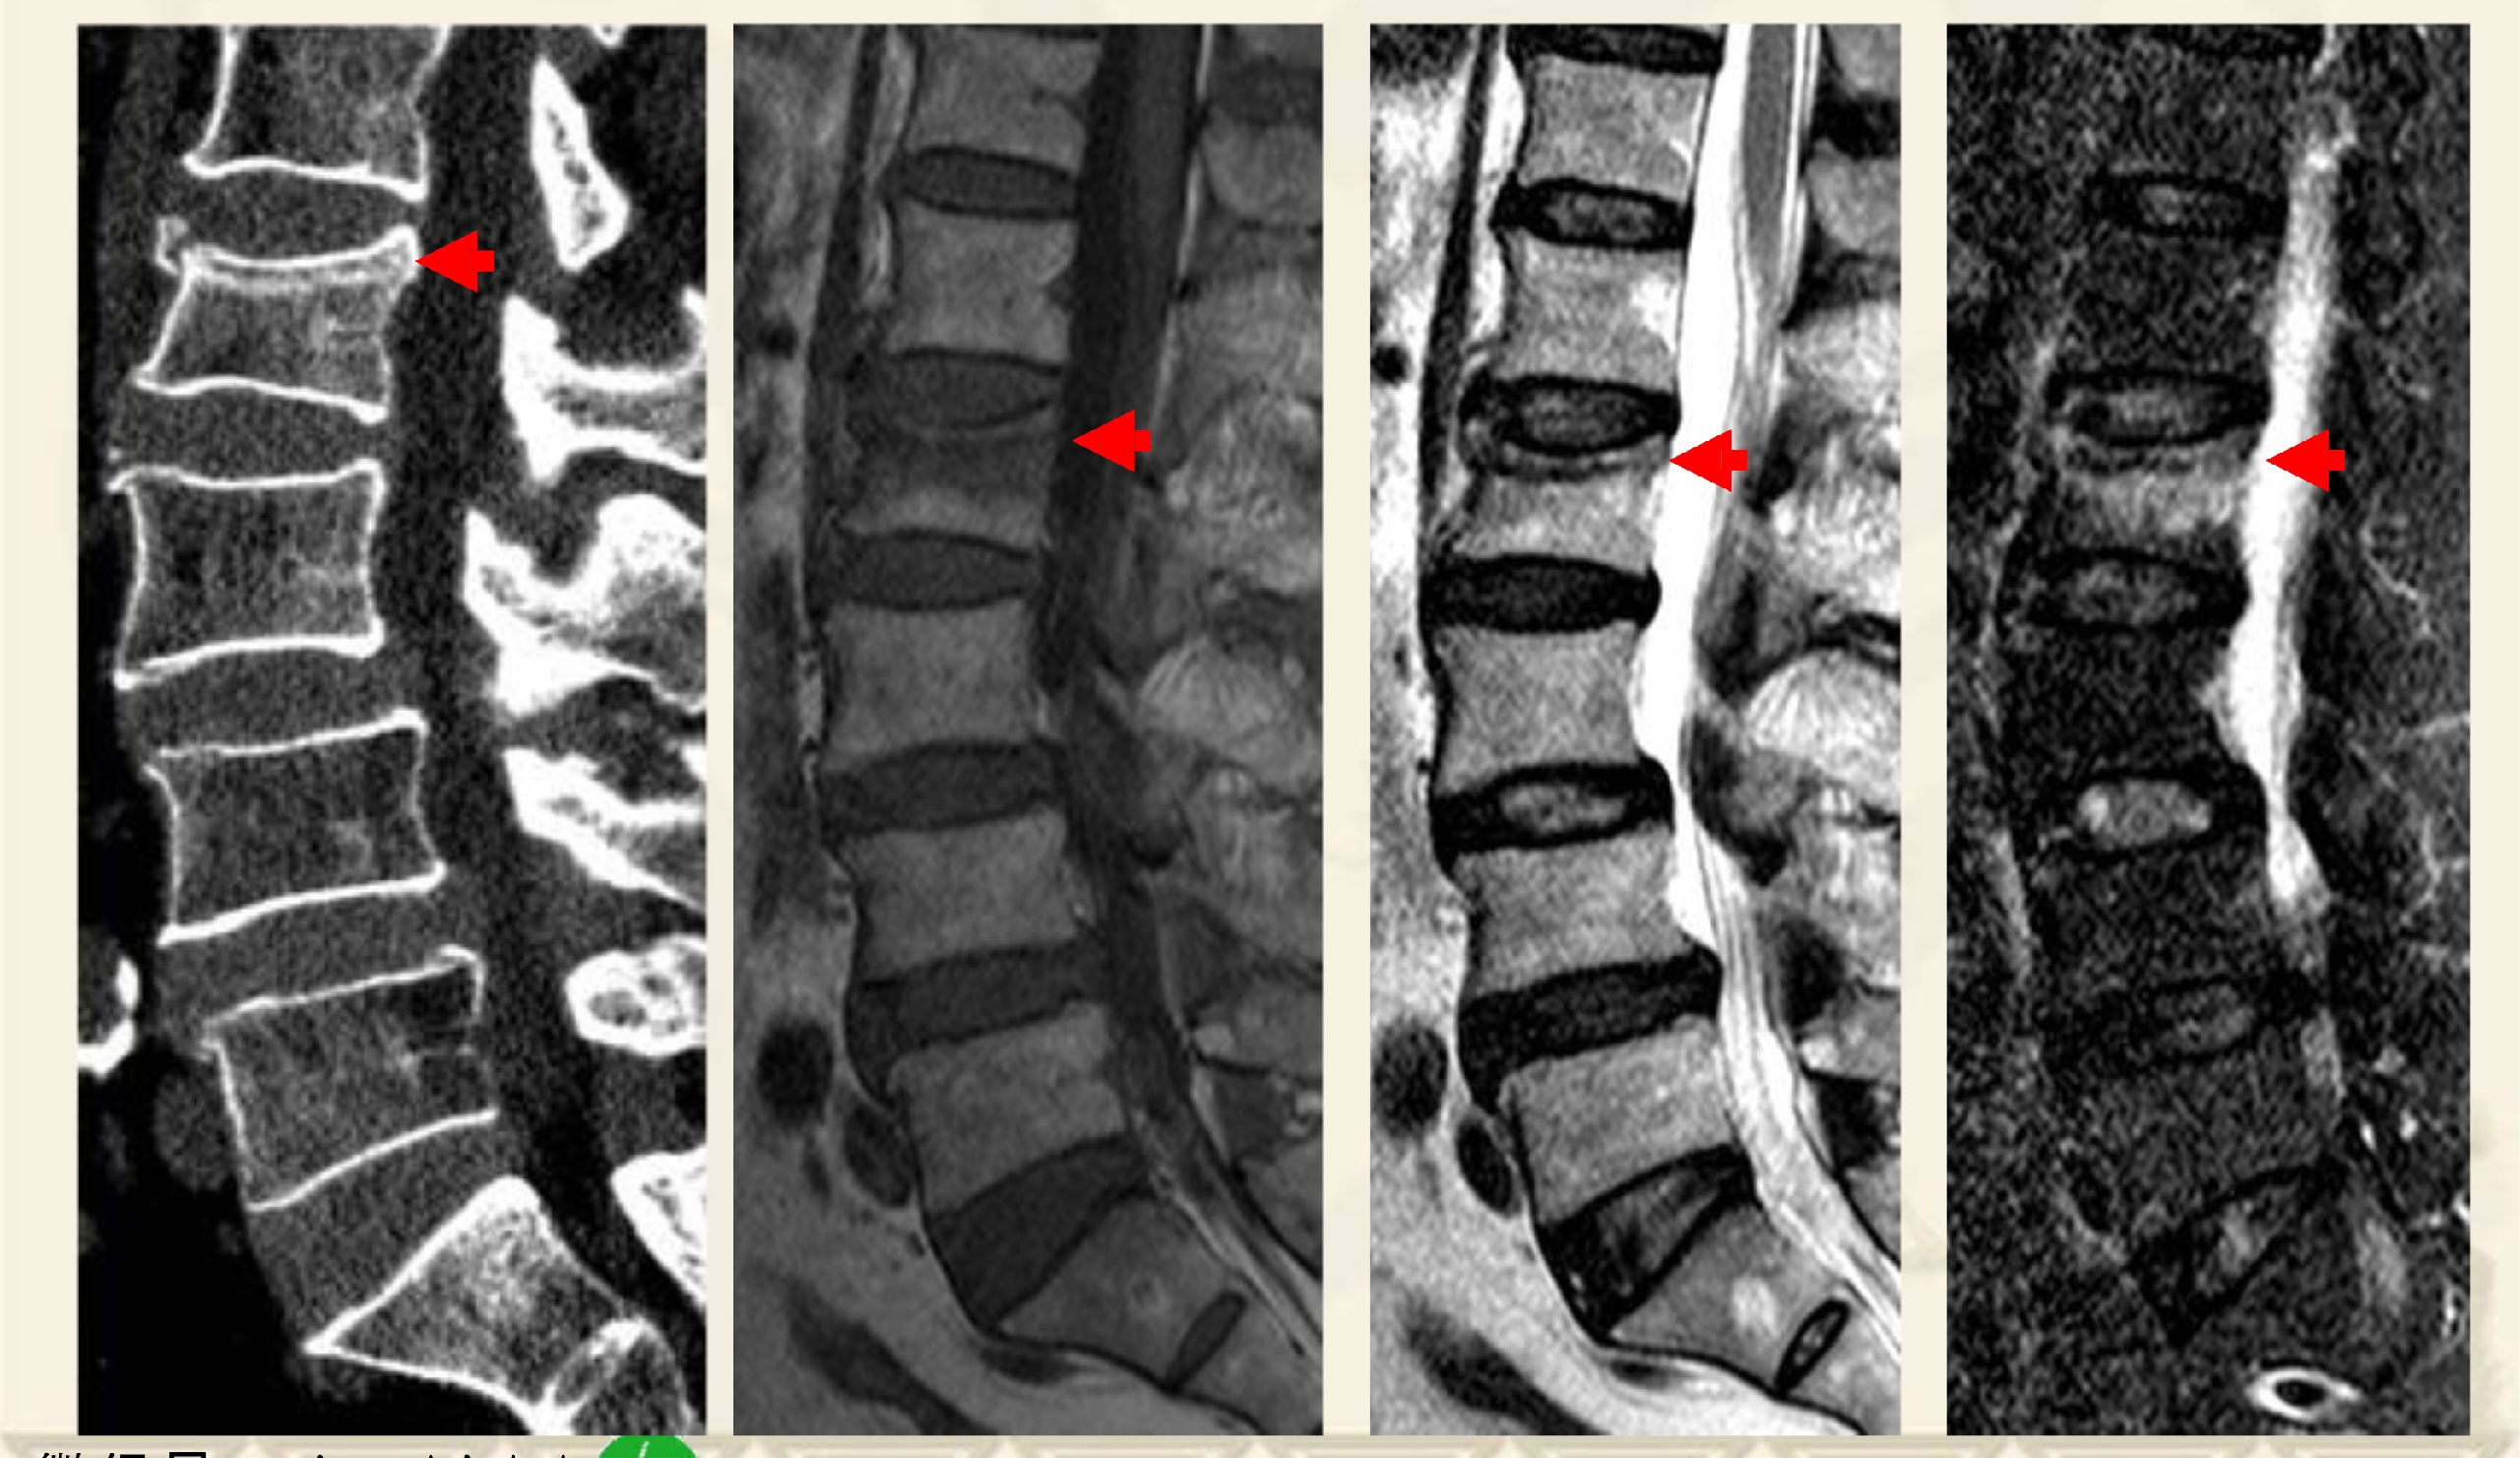

如何定位OVCF的骨折线

两大类型:①压缩后嵌插型,②压缩后自动复位裂隙型

压缩后嵌插型骨折线,CT:高密度带、MRI低信号带。

压缩后自动复位裂隙型,CT:裂隙,MRI:低信号区(气体)

术前CT

术中透视图

透视引导下,经椎弓根入路或根旁

靶向骨折区置管

术后X线

术后CT